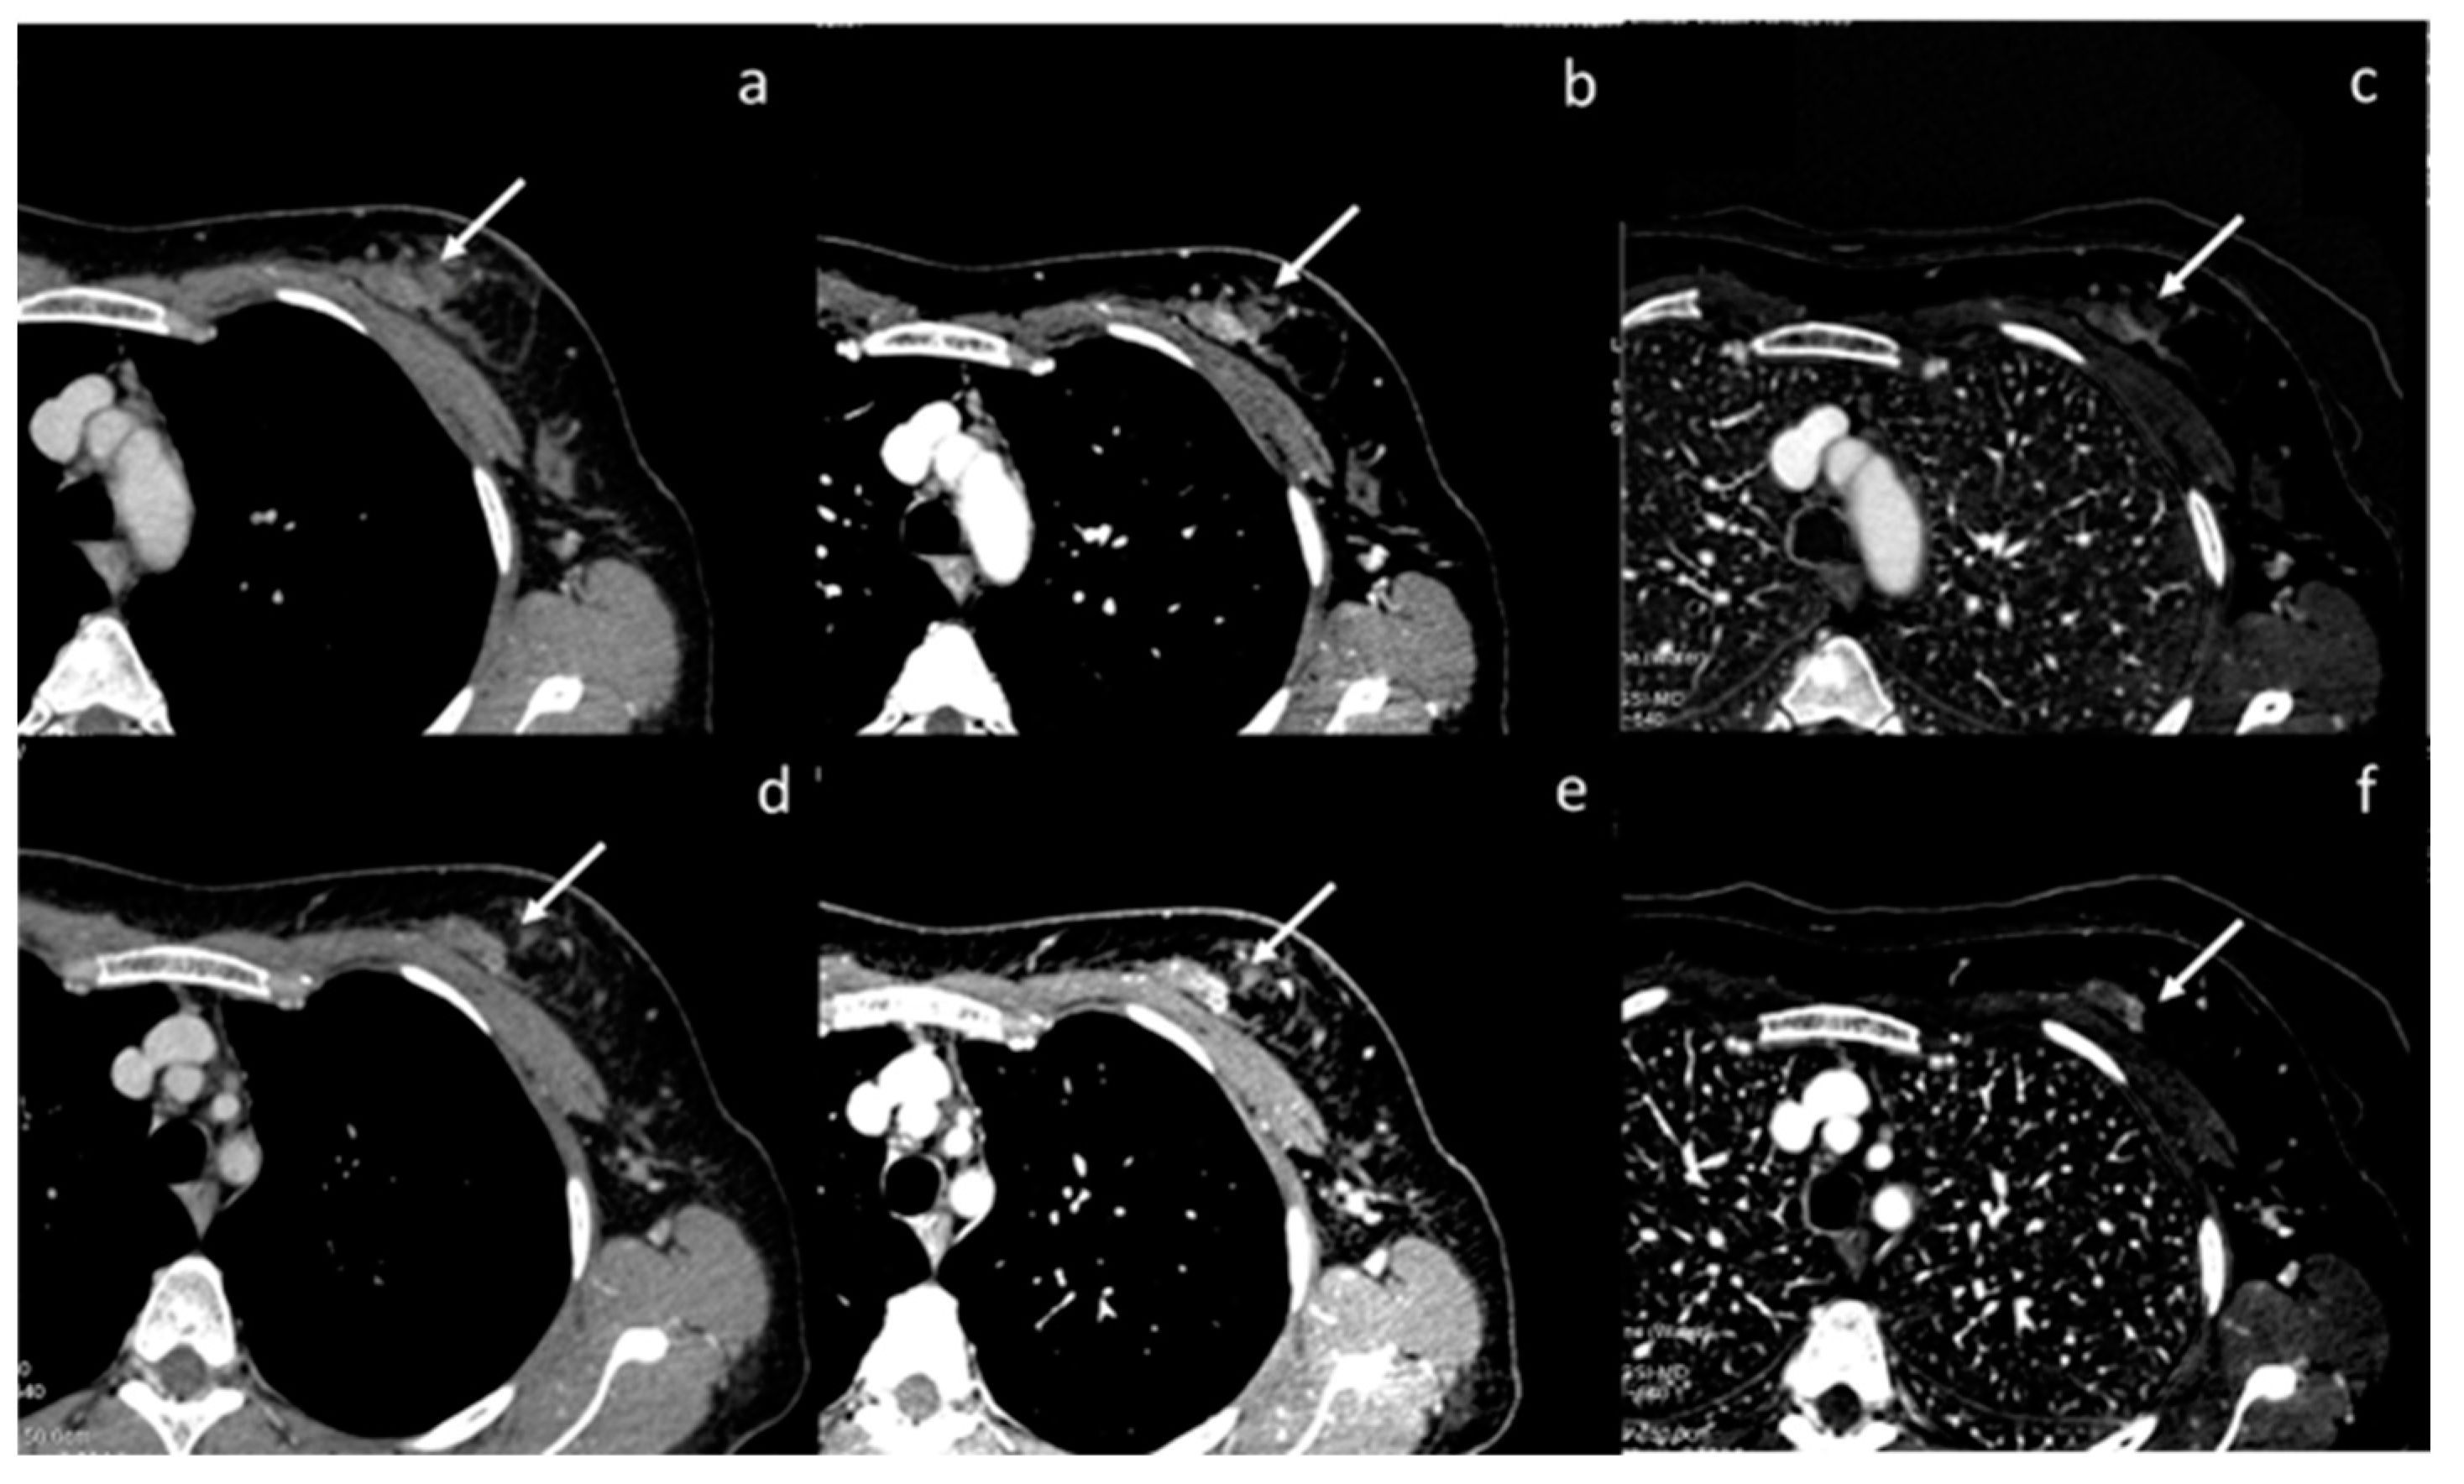

- Volterrani, L.; Gentili, F.; Fausto, A.; Pelini, V.; Megha, T.; Sardanelli, F.; Mazzei, M.A. Dual-Energy CT for Locoregional Staging of Breast Cancer: Preliminary Results. Am. J. Roentgenol. 2020, 214, 707–714. [Google Scholar] [CrossRef] [PubMed]

| Volterrani et al. [57] Retrospective study | Italy | To demonstrate the feasibility of DECT for locoregional staging of breast cancer and differentiation of tumor histotypes | 31 | Discovery CT 750 HD, GE Healthcare No C.I. | DECT is feasible and seems to be a reliable tool for locoregional staging of breast cancer. |